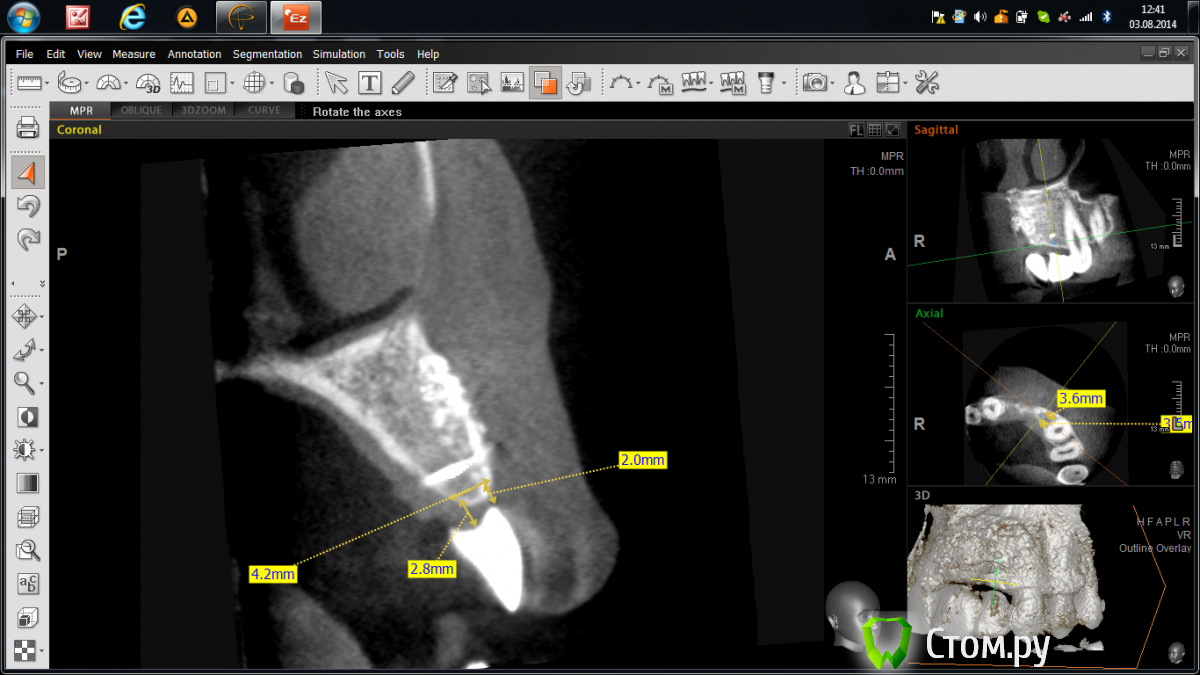

Abuk Опубликовано 3 августа, 2014 Поделиться Опубликовано 3 августа, 2014 Добрый день,коллеги.Горит,помогайте! Года 2 назад,когда я был молод,красив и малоопытен)),консультировал пациентку,на предмет восстановления имплантатами двух отсутствующих зубов:2.1,2.2; на месте которых висел композитный пртез. Отрофия кости была заметна невооруженным глазом,КТ подтвердило. Начинали с 3D пластики.Старые фото, пока, не нахожу((( Ширина кости была около 3 мм по 11-13 мм гребню.После операции ,спустя 4 месяца,пациентка ушла в декрет и пропала на 2 года.Ныне сделав рентген - шаблон,отправил на КТ(.Ошибки я учел,по поводу костной пластики).Недостаток в верхушке гребня и воостановление десневого сосочка-задачи,которые предстоит решить.Посоветуйте:возможно ли1.без повторной агрессивной костной пластики2.или можно ограничиться только работой с мягкими тканями???????? Ссылка на комментарий

Mane Опубликовано 3 августа, 2014 Поделиться Опубликовано 3 августа, 2014 Устанавливайте два тонких имплантата размером до 3,5 мм в диаметре. Если проходят по канонам.Сразу естесственно с расщеплением и направленной костной регенерацией и десневой аугментацией. Задача не топить платформу импланта в кость. Установить имплант в уповень с костью. И далее вторым этапом через 6 мес открытие имплантов с пластикой сосочков. Возможно повторная десневая аугментация. 2 Ссылка на комментарий